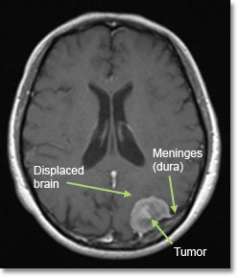

A meningioma is a tumor that arises from a layer of tissue (the meninges) that covers the brain and spine.

Meningiomas grow on the surface of the brain (or spinal cord), and therefore push the brain away rather than growing from within it. Most are considered “benign” because they are slow-growing with low potential to spread.

- Magnetic resonance imaging (MRI) scans effectively detect most meningiomas and are best at displaying details of the brain.